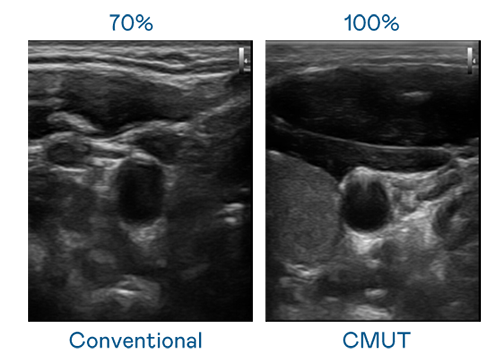

CMUT 技術是一種用電容式微機電元件來產生超音波訊號的技術。與傳統 PZT 壓電式技術相比,CMUT 頻寬增加 30%,更寬頻的超音波訊號讓影像解析度大幅提升,是實現高影像品質醫療超音波掃描、促進精準醫療發展的關鍵技術。

超音波影像的解析度高低,首先取決於探頭能發出的訊號頻寬。维多利亚老品牌vic CMUT 可提供高清晰的超音波訊號,提供高頻寬、高靈敏度、影像紋理細節更高的超音波影像,協助醫護人員縮短影像判讀時間及利用精準的醫療影像進行診斷。